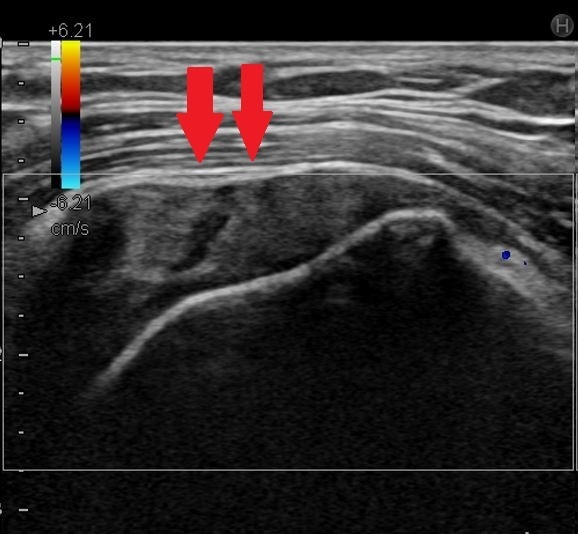

超音波画像( 赤矢印 に陥凹があり断裂を疑う)